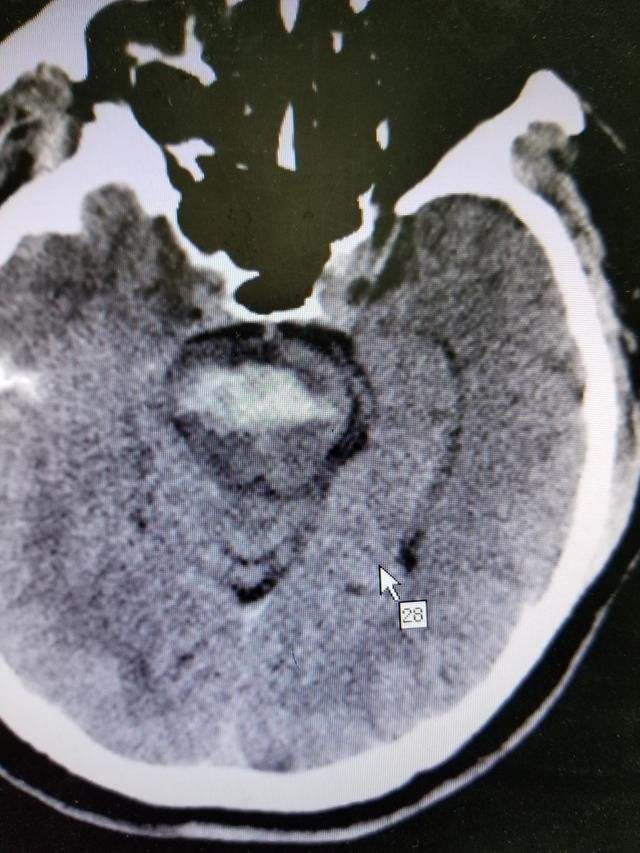

患者被紧急送到医院确诊为脑干出血,患者的呼吸和心率已经受到影响。

医生告诉患者的儿子:“主要的出血部位是脑干的延髓。”

脑干出血非常凶险,特别是延髓部位的,因为这里有呼吸循环中枢,出血后往往会导致患者的呼吸和心跳。

4、脑干并不是一个部位,它包括中脑,脑桥,延髓三部分,不同部位出血症状是不一样的,但这些地方都很重要,一般如果出血5毫升以上就算出血量大的,预后相对较差。